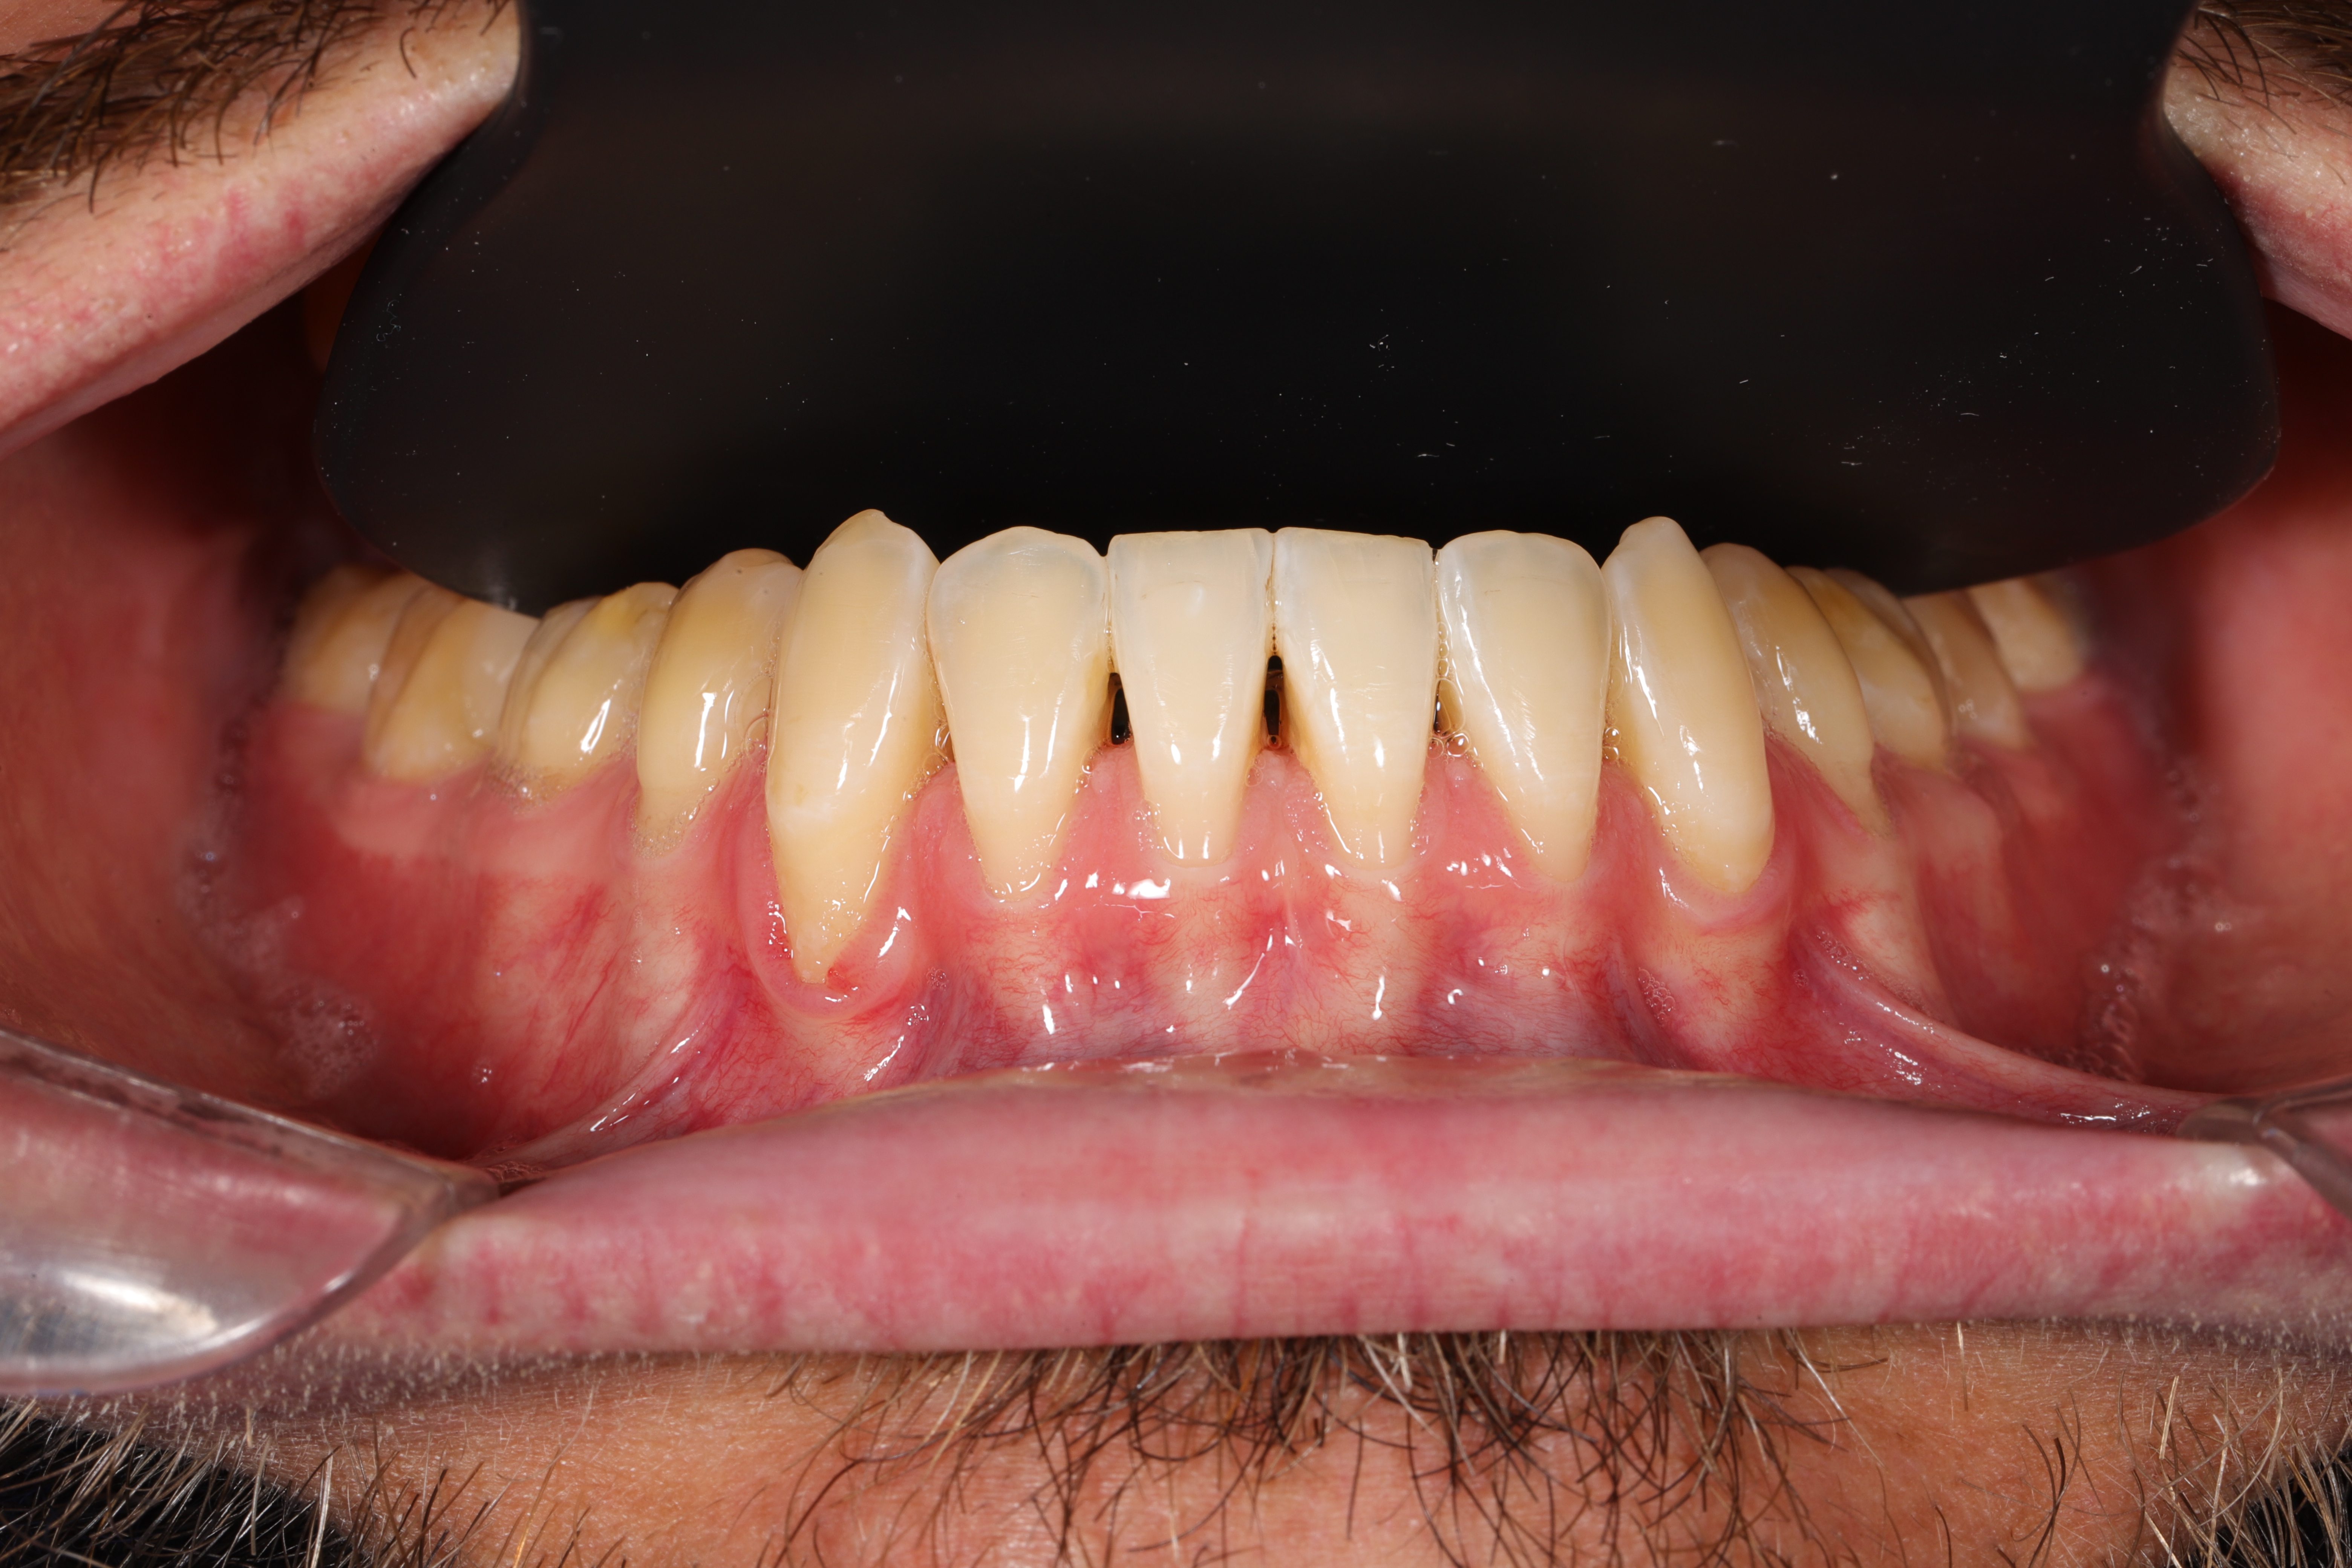

Gingival recession is the apical displacement of the gum margin, which exposes part of the tooth root.

• Root hypersensitivity and/or root caries due to gum recession.

• Aesthetic concerns (receding gums, visually elongated teeth).

• Thin gingival biotype and risk of further gum recession.

• Coronally Advanced Flap (CAF): The gum tissue is gently repositioned coronally (toward the tooth crown) to cover the exposed root.

• Connective Tissue Graft (CTG): Often used as an additional graft, it is harvested from beneath the patient’s palate and placed under the flap to increase tissue thickness and achieve complete root coverage.

• “Gold Standard”: The combination of CAF + CTG is considered the most effective method for achieving full root coverage, restoring a natural gum contour, and preventing further periodontal issues.